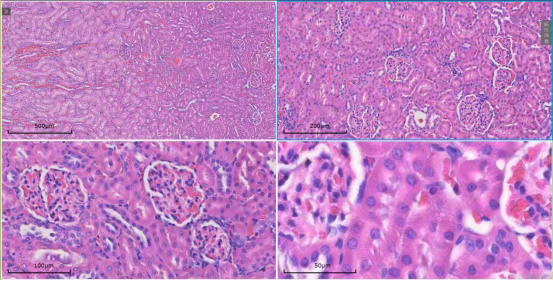

肾脏切片扫描

• 4倍:清晰划分肾皮质、髓质、肾锥体等大结构区域。

• 10倍:展示肾小球在皮质中的分布情况。

• 20倍:观察肾小管(近曲小管、远曲小管)的细胞形态与管腔结构。

• 40倍:精细解析肾小球毛细血管袢结构及足细胞形态。

57487c69-29c7-442d-821e-2b628d45a358.png

肾4-40倍